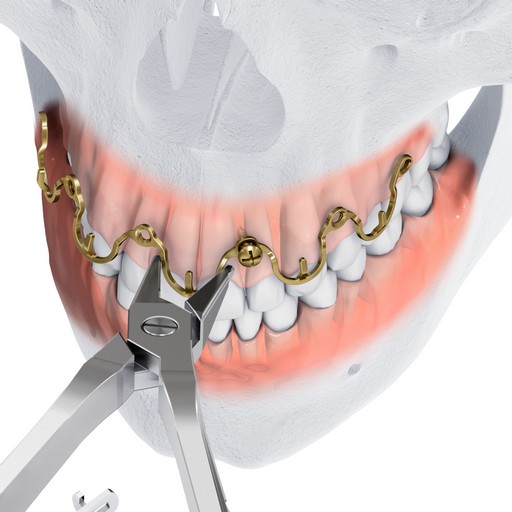

Maxillomandibular fixation can be achieved more quickly using the Matrix WAVE plate than by using arch bars. Removal is simple, and can be done in a non-OR setting. The MatrixWAVE plate design eliminates the need for circumdental wiring. This has several advantages, including reduced risk of needle stick-like injuries and reduced risk of tooth loosening. Additionally, the MatrixWAVE MMF system covers less tooth surface, allowing more access to the teeth for cleaning. The design of the plate maximizes patient comfort, as it has rounded, smooth edges. The screw heads are also rounded, and the plate hooks can be bent towards the gingiva after wiring.

The MatrixWAVE plate was attached to the maxilla with screw placement in the inter-root spaces (Fig 2). A second MatrixWAVE plate was attached in corresponding position to the mandible, with screw placement in the inter-root spaces (Fig 3). Wires were placed around the plate hooks to bring the dental arches into occlusion. Note the preexisting anterior open bite (Fig 4). Careful adjustment of the MatrixWAVE plate and wiring in the region of the mandibular fracture allowed the bone fragments to be precisely aligned without the requirement for screw repositioning (Fig 5). The postoperative panoramic x-ray (Fig 6) shows the two MatrixWAVE plates in situ, with other plates used to fixate the left mandibular angle fracture. Note that a portion of the Matrix- WAVE plate was removed from the left molar region in the mandible (Fig 6).